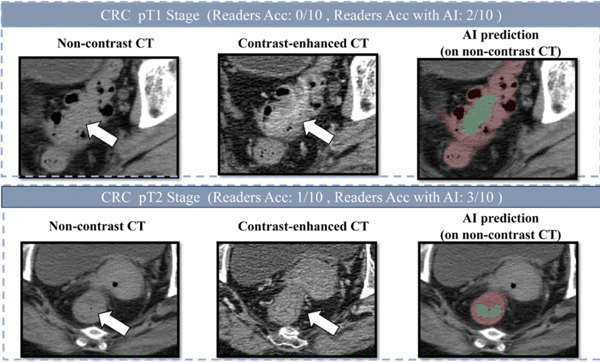

肠癌病灶在平扫CT、增强CT和AI画面上的表现

研究团队发表在欧洲肿瘤内科学会官方期刊《肿瘤学年鉴》(Annals of Oncology,影响因子65.4)上的论文显示,DAMO COCA模型的敏感性(即防止漏诊的能力)达到86.6%,特异性更达到99.8%,即误诊率仅有0.2%。与10名不同年资的影像科医生相比,DAMO COCA模型的敏感性显著高出20.4%,在乙状结肠、直肠等易漏部位上的表现尤为突出。而在AI辅助下,医生的敏感性和特异性可分别提高14.5%和3.1%,有效减少临床漏诊。